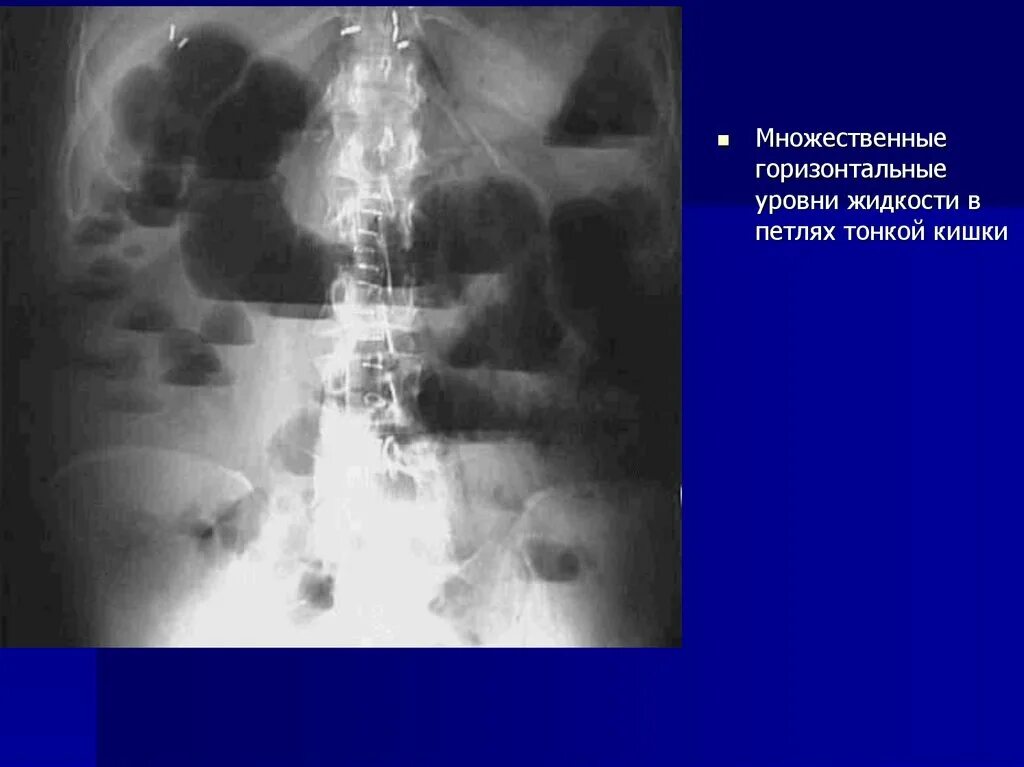

Симптом чаши